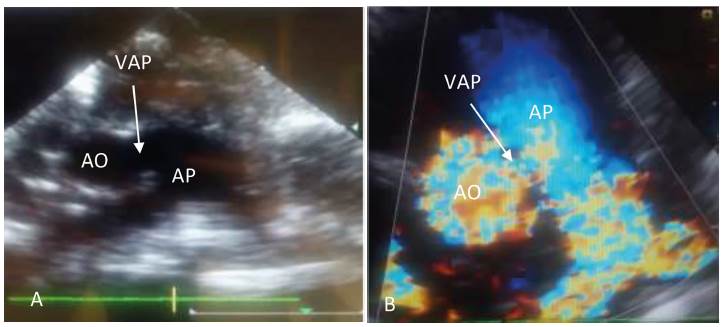

Paciente femenina de 50 días de nacida, quien ingresa a la institución el 8 de noviembre de 2016 por taquipnea, diaforesis predominante durante la lactancia y pobre ganancia ponderal, síntomas presentados desde el nacimiento. El examen físico reveló taquipnea, soplo cardíaco continuo en focos de la base, con S2 reforzado, crépitos finos en ambos campos pulmonares y hepatomegalia congestiva. Adicionalmente rasgos dismórficos, ductus arterioso permeable y displasia multiquística renal izquierda. Ingresa con peso de 2080 gramos, con cuadro clínico compatible con insuficiencia cardíaca congestiva, que ameritó ingreso a unidad de cuidados intensivos. El ecocardiograma doppler color de ingreso evidencia situs solitus, cavidades izquierdas dilatadas con función sistólica conservada, presencia de una ventana aortopulmonar tipo I, foramen oval permeable con cortocircuito de izquierda a derecha, insuficiencia tricuspídea moderada, insuficiencia mitral severa e hipertensión pulmonar severa. Durante estancia en cuidado crítico cursa con sepsis, la cual fue modulada con antibioticoterapia de amplio espectro. Como complicaciones presentó enterocolitis necrotizante y hemorragia de vías digestivas, además de una crisis epiléptica, las cuales fueron manejadas con éxito. El 28 de noviembre de 2016, al superar procesos infecciosos concomitantes, es llevada a procedimiento quirúrgico, con peso de 1976 gramos. Se realiza reparo de ventana aortopulmonar (tipo I con coronaria derecha originada en el lado pulmonar de la ventana - abordaje transaórtico) más cierre de conducto arterioso (3 mm de diámetro); ameritó asistencia ventilatoria mecánica durante 72 horas posteriores. El ecocardiograma doppler color postoperatorio revela reparo aortopulmonar sin cortocircuito residual, foramen oval permeable con cortocircuito de izquierda a derecha, cavidades izquierdas dilatadas con disfunción sistólica leve, insuficiencia tricuspidea moderada y mitral severa; sin signos de hipertensión pulmonar. Durante el postoperatorio presenta nueva crisis epiléptica, episodio de bradicardia sinusal y síndrome broncoobstructivo, los cuales fueron tratados, con evolución favorable. Egresa de la institución el 12 de diciembre de 2016, con peso de 2000 gramos.

La ecocardiografía doppler es clave para la detección, teniendo en cuenta que la radiología y electrocardiografía son inespecíficas. En el caso referido hubo alta concordancia diagnóstica ecocardiográfica con los hallazgos intraoperatorios. Sin embargo, los falsos positivos o negativos pueden existir, en especial cuando coexisten anomalías complejas asociadas, por lo cual en muchos casos se requiere el cateterismo cardíaco 3.

La VAP es una cardiopatía congénita infrecuente. En nuestro caso, la ecocardiografía jugó un papel crucial en el diagnóstico. Se realizó una intervención quirúrgica oportuna, por vía transaórtica, en lactante menor con peso inferior a 2000 gramos, con el fin de minimizar el riesgo de progresión a enfermedad vascular pulmonar irreversible, con resultados favorables.